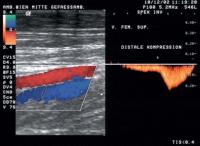

Duplexsonographie - Kompression

Abbildung 7: Nach distaler Kompression Zunahme des Flusses im Doppler

Keywords: DuplexsonographieFarbdopplerFlussKompression